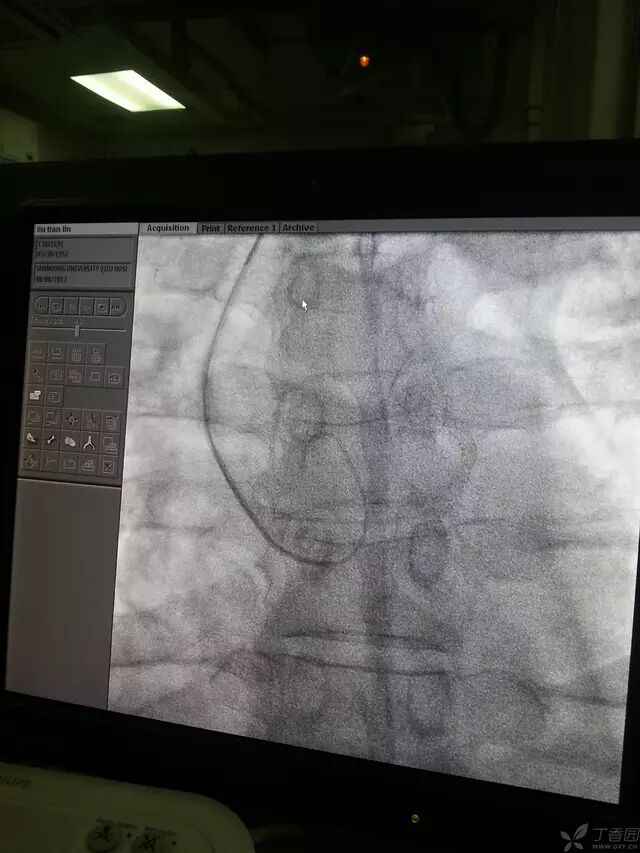

然后导管跟进,固定导丝,进入窦底,导管进入如图时可回撤导丝。

造影导丝是什么原来心脏造影这样做:冠脉造影全程图解_https://www.jmylbn.com_新闻资讯_第13张